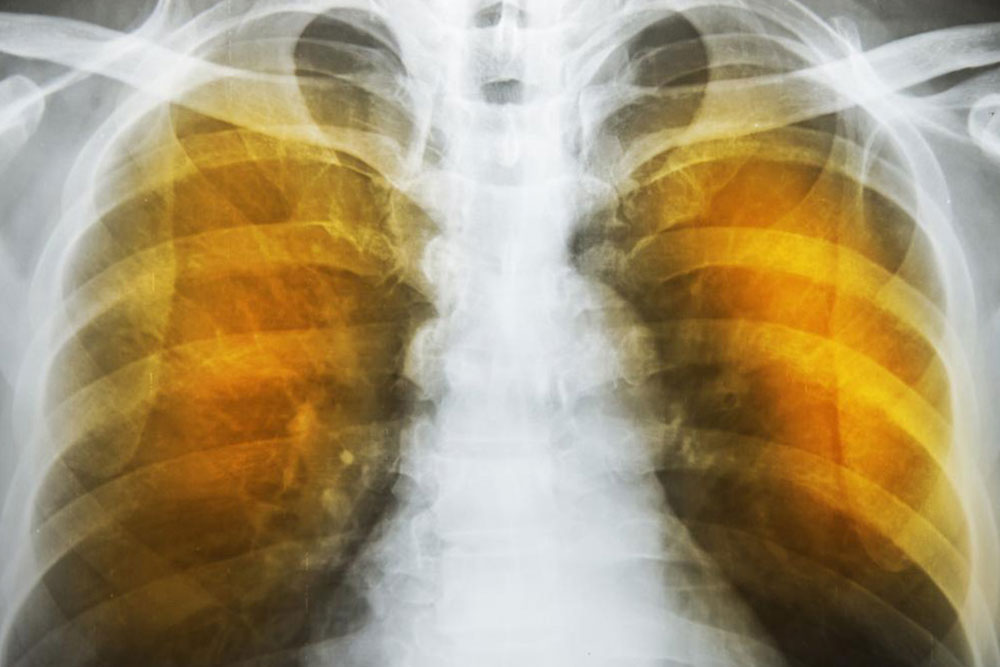

As the deterioration continues, the alveoli lose their strength and start rupturing. In extreme cases, there may be large scale destruction which leads to empty spaces in lungs called bullae. This would reduce the functional area of the lung which in extreme cases call for surgical removal. In an extremely rare condition, large scale rupture of alveoli can cause a condition called pneumothorax and the collapse of the lung, a very serious condition, which can be fatal. The best thing one can do is stop exposure to irritants.